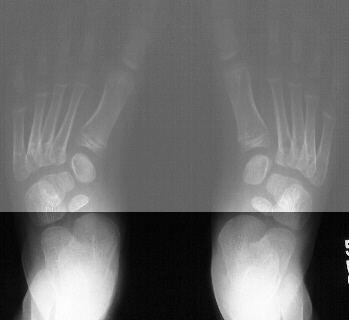

deformity. His subtalar motion was maintained. AP and lateral standing

radiographs were obtained.

Radiographic Evaluation

- No universally accepted clinical or radiographic criteria for defining

relationships of forefoot and hindfoot in flatfoot, skewfoot, or metatarsus

adductus- how much forefoot adduction needed to reclassify flatfoot as

skewfoot?

- Medial angulation of the talus-1st metatarsal line - indicative

of forefoot adduction

- Increased Kite's talocalcaneal angles on AP(>35) and lateral(>45)-

indicative of hindfoot valgus

- Lateral subluxation of navicular bone on talus